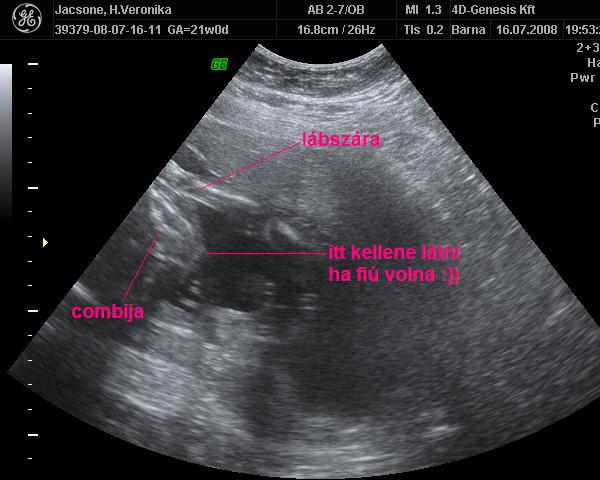

A mávban volt az uh. Hát igen, az sem kutya hogy lesni kell hgoy valamit láss

Így meg nincs értelme elmenni 4d-re ha megint alig látunk valamit

Asszem elmegyek belgyógyászatra nemsokára az sztkba, ismi az uh-s belgyógyis doki és mozizunk egyett

persze az nem 4d de ingyé lesz